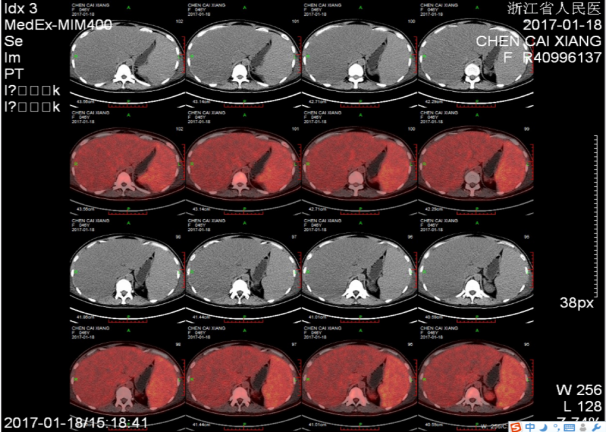

2017-01-18行PET-CT检查提示:

脾肿大伴FDG代谢活跃,SUV最大值约4.5,血液系统疾病可能,必要时活检;全身骨弥漫性FDG代谢活跃,SUV最大值约4.8,请结合骨穿。

左颈部、腹膜后和腹腔内散在淋巴结,FDG代谢活跃,反应性表现可能,请结合脾脏病理考虑。

脂肪肝,肝肿大,请结合临床。

双侧胸腔积液,双下肺少许不张。慢性胆囊炎。腹盆腔积液。盆腔左侧囊性灶,FDG代谢未见异常,考虑良性,卵巢囊肿首先考虑。全身多发皮下水肿。双肾和双侧输尿管显像剂排泄缓慢(图3)。

图3